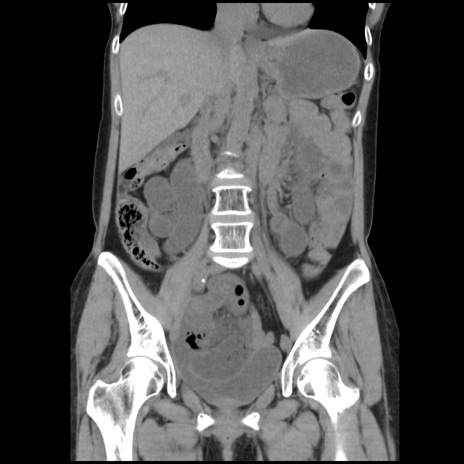

症例32(冠状断像)

【症例】40歳代 女性

【主訴】上腹部痛、嘔気・嘔吐

【現病歴】約9時間前頃から急に上腹部痛、嘔気、嘔吐が出現。改善しないため救急要請。

【既往歴】子宮頚癌(広汎子宮全摘術、放射線療法)、腸閉塞

【身体所見】腹部:平坦、軟、腸雑音亢進、上腹部を中心に腹部全体に圧痛あり。

【データ】WBC 8400、CRP 0.03